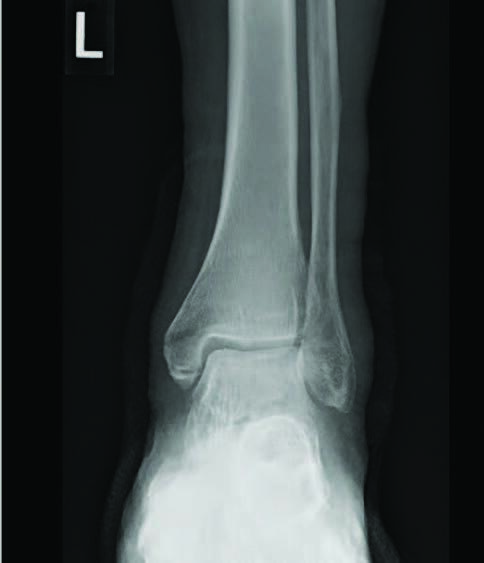

Regardless of medical history, surgical versus non-surgical management of ankle fractures depends on fracture pattern, stability and displacement. However, it is thought that these factors carry a different weight in patients with complicated diabetes.4 An important factor in determining surgical necessity for ankle fractures is the computed tomography (CT) scan. Liberal use of CT is recommended for evaluation stability and displacement of ankle fractures, especially in those with diabetes.4 In fact, Kumar and team found that ankle fracture management changed in more than 23 percent of cases after CT examination of the injury. This study did not focus on diabetic ankle fractures, however use of CT becomes even more important in compromised patients.5

Newer literature does suggest operative management for diabetic ankle fractures primarily due to unacceptably high levels of complications with non-operative cast immobilization. Lovy and coworkers noted a complication rate for non-operative treatment of 75 percent, compared to 12.5 percent with operative treatment in displaced diabetic ankle fractures.6 Complications included nonunion, malunion, cast ulcerations, new onset Charcot arthropathy, unplanned operations (e.g. ORIF of fracture at least six weeks after initial injury) and deep infections.6 However, patients with stable isolated malleolar fractures can be managed conservatively via immobilization.4 Such cases however, warrant monitoring at 14-day intervals with serial imaging and thorough examinations to ensure appropriate recovery without early displacement, Charcot development or other skin complications.4